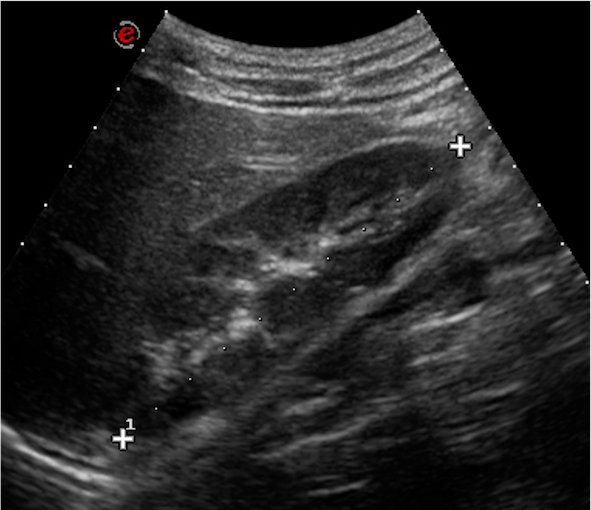

Gli esami di laboratorio portati in visione mostrano una funzione renale normale (creatinina 0,65 mg/dl, eGFR sec. Schwartz 148 ml/min/1,72 m2), con rapporto proteinuria/creatininuria pari a 600 mg/g (vn < 200 mg/g). Nella norma anche lecografia addominale. Programmato un successivo controllo per approfondire il quadro, il ragazzo viene intanto valutato presso unaltra sede, dove lo studio delle urine delle 24 ore mostra una proteinuria in range non nefrosico (410 mg/24h) con calcio, fosforo, ossalati, acido urico e citrato urinari tutti nella norma; allecografia addominale riscontro di nefro-calcinosi a carico del rene sinistro.

Dopo tre mesi il ragazzo ritorna presso il nostro ambulatorio: la proteinuria appare in netto peggioramento (1344 mg/24h), sempre accompagnata da microematuria, mentre si esclude una proteinuria ortostatica. Gli esami ematochimici eseguiti, comprensivi di emocromo, funzionalità renale ed epatica, assetto lipidico e proteico, complemento, indici di flogosi e autoanticorpi (ANA, anti-dsDNA, ANCA), risultano tutti nella norma. Allecografia delladdome confermati spot iperecogeni bilaterali come da nefrocalcinosi (Figura 1).